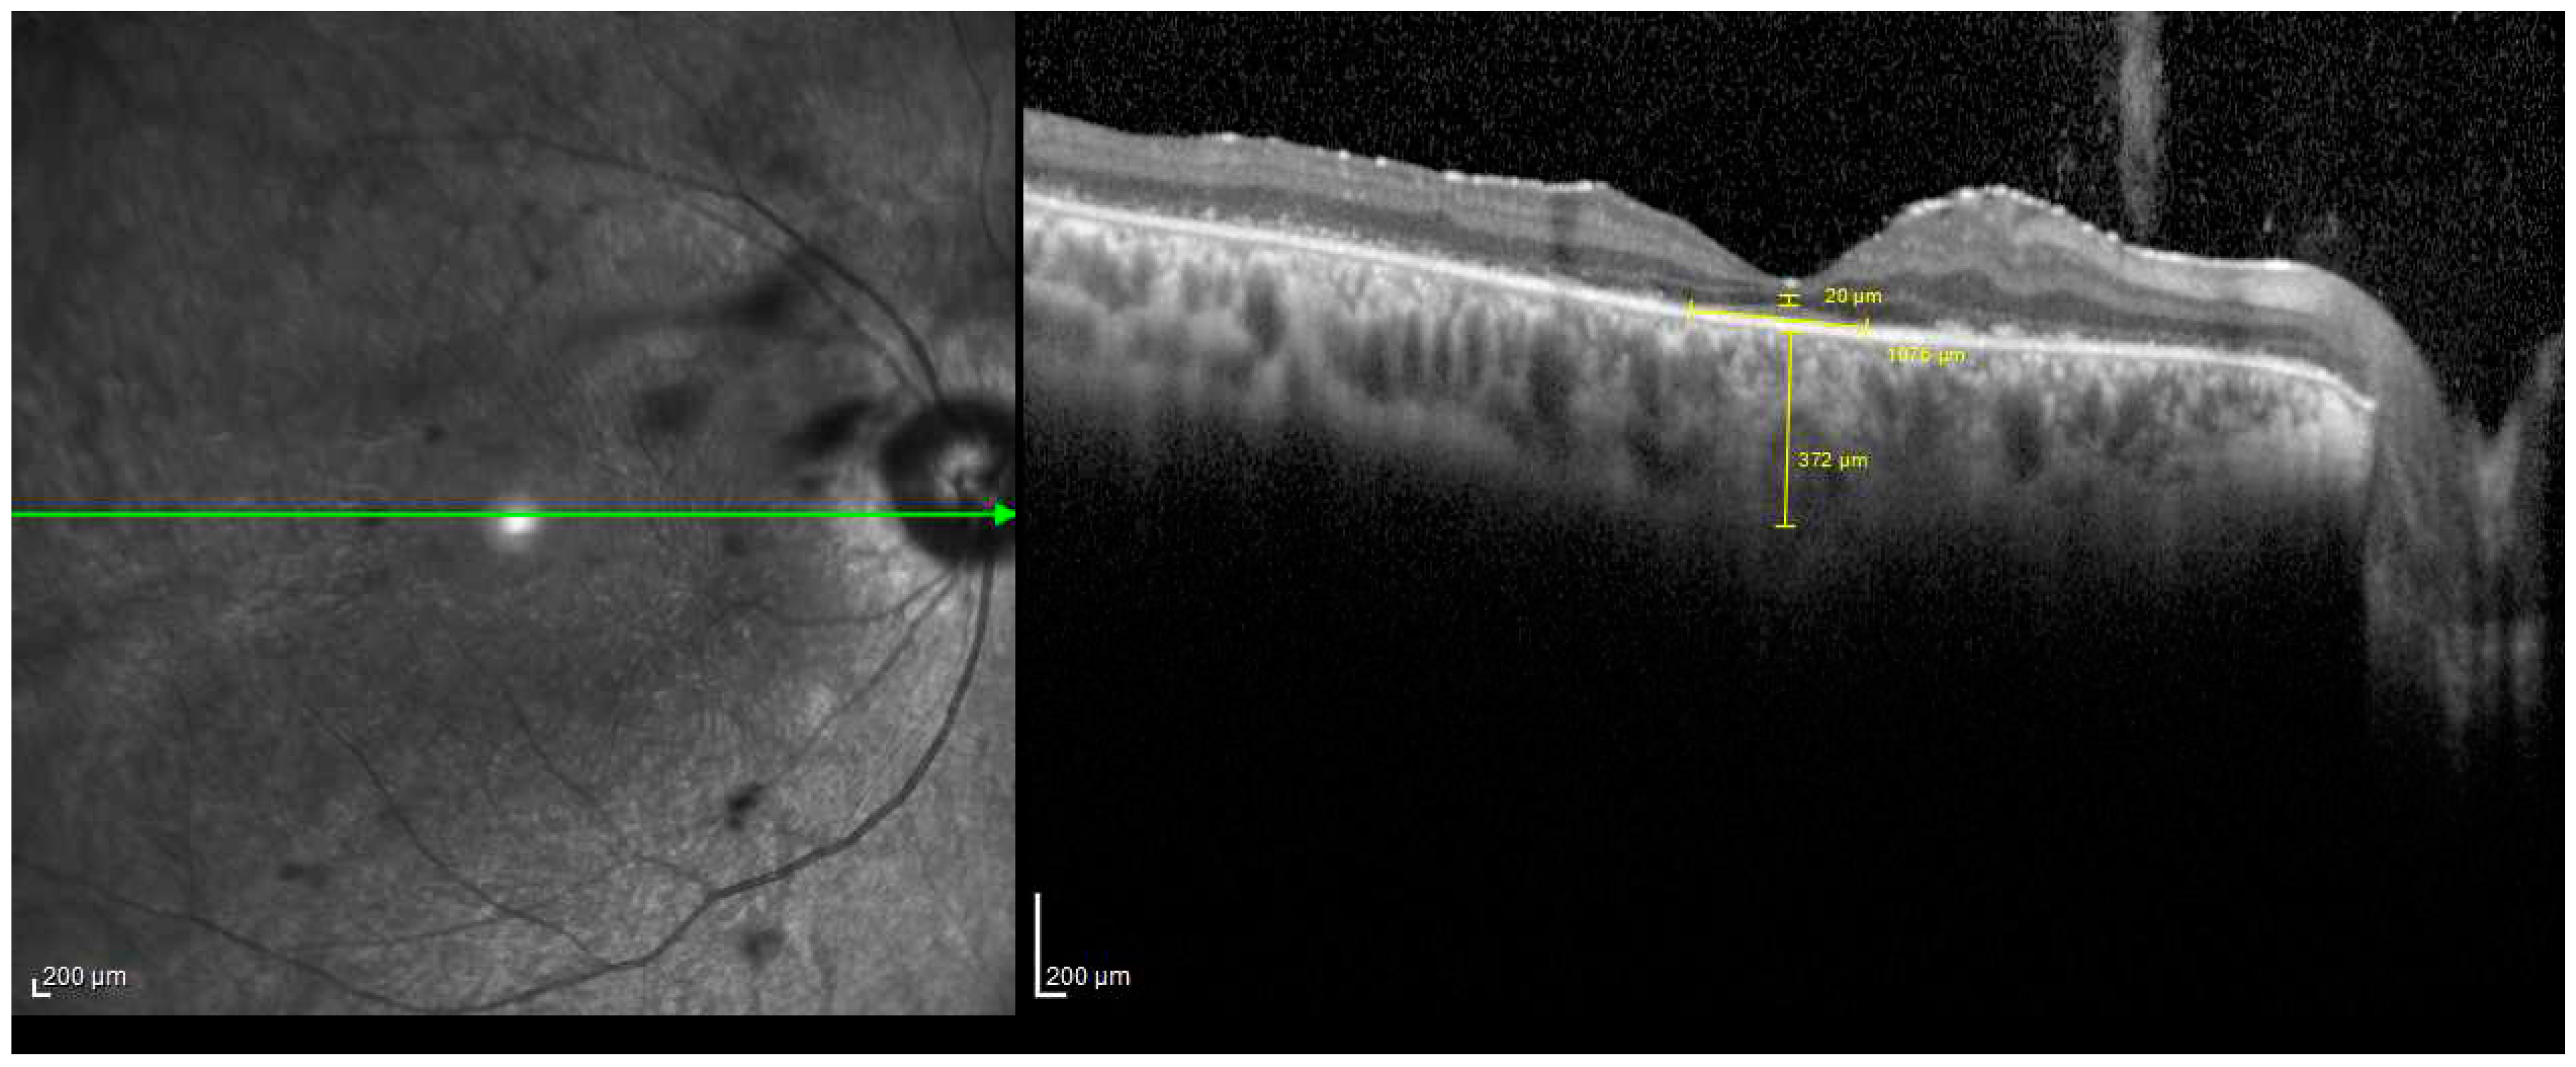

2.2. SD-OCT Measurements

- VMT: presence of perifoveal vitreous cortex detachment from the retinal surface, with macular attachment of the vitreous cortex within a 3 mm radius of the fovea associated with distortion of the foveal surface, intraretinal structural changes, and/or elevation of the fovea above the RPE.

- FTMH with VMT: a full-thickness foveal lesion that interrupts all macular layers.

- The holes were classified by size as small holes (<250 μm), medium (250–400 μm), or large (>400 μm).

- Small, medium, or large FTMH without VMT.

- Lamellar macular hole (LMH): characterized by an irregular foveal contour, inner retina defect, intraretinal splitting (schisis), and an intact photoreceptor layer.